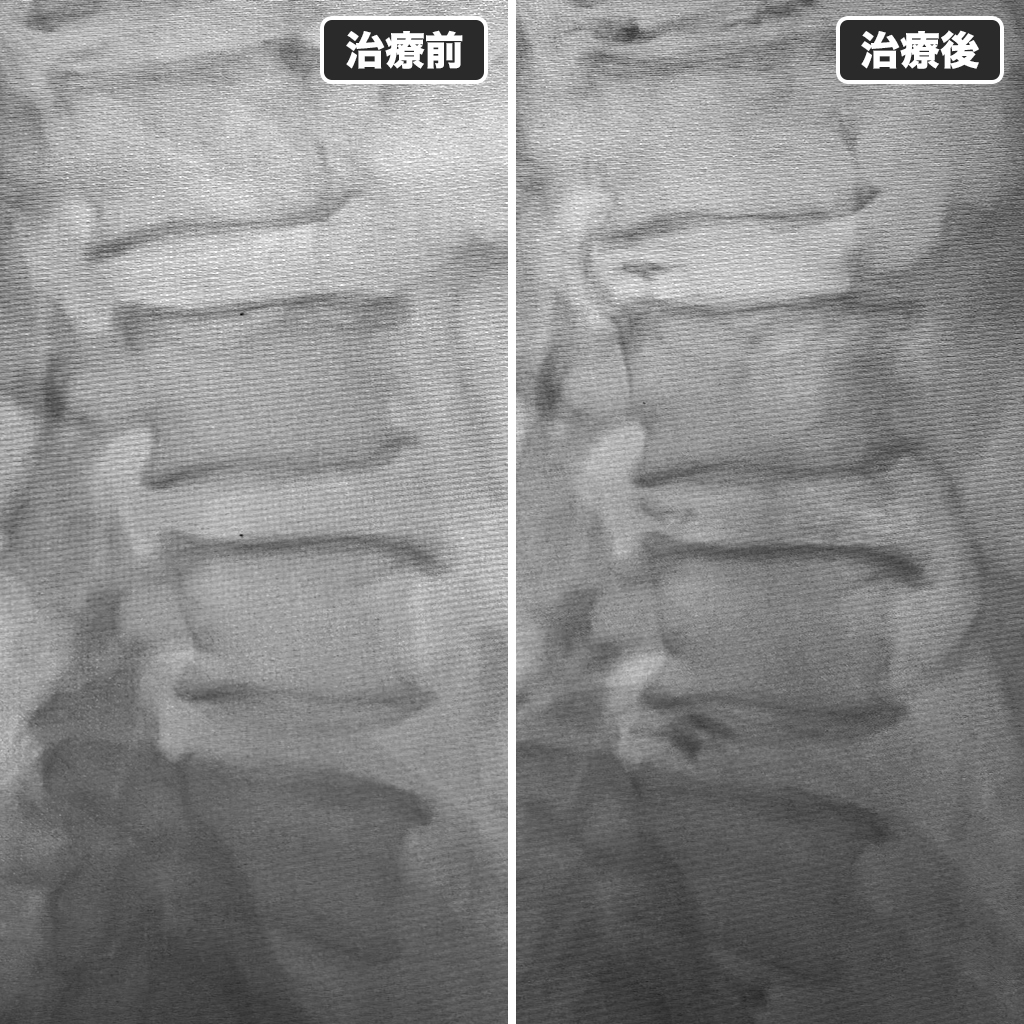

治療前後のレントゲン写真

治療前後のレントゲン写真です。左側が治療前で右側が治療直後になります。